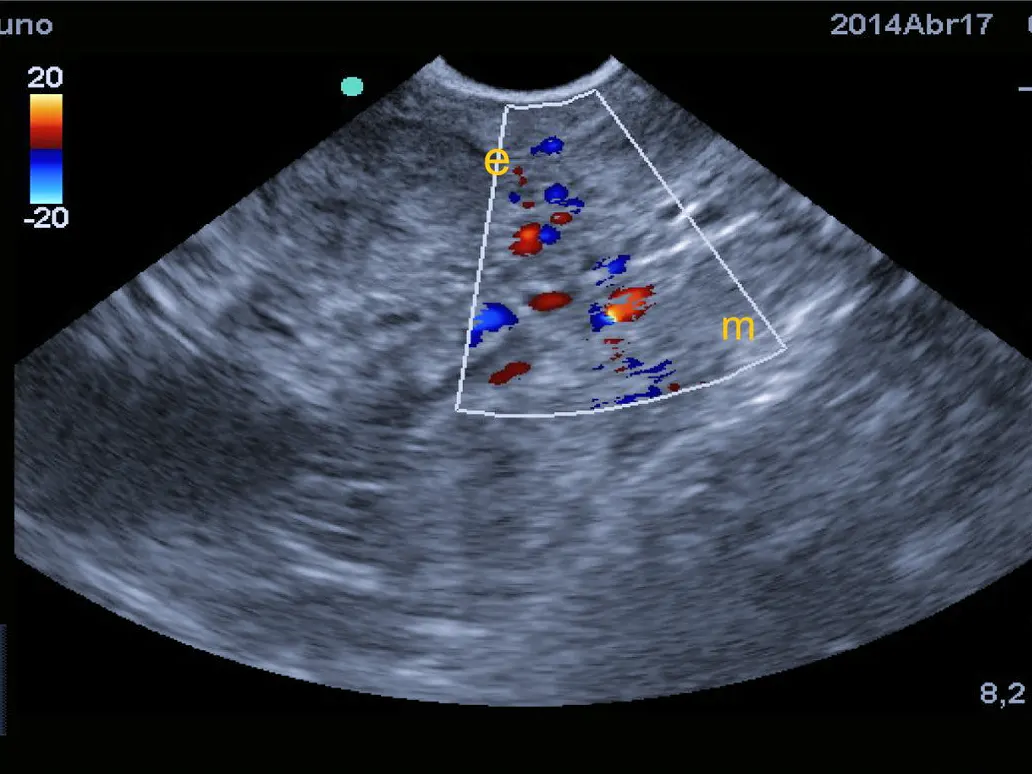

Ultrazvučna pretraga je važan dijagnostički alat u veterinarskoj medicini jer omogućuje veterinarima da dobiju detaljan uvid u unutarnje strukture tijela bez potrebe za invazivnim postupcima.

Tijekom ultrazvučne pretrage dio tijela je izložen bezopasnim, visokofrekventnim zvučnim valovima kako bi stvorio slike unutarnjih struktura tijela na ekranu uređaja.

Tako uživo možemo vidjeti kretanje, funkciju i strukturu unutarnjih organa vašeg ljubimca.

UZV se koristi u svrhu dijagnostike bolesti svih organa trbušne šupljine, srca i krvožilnog sustava.